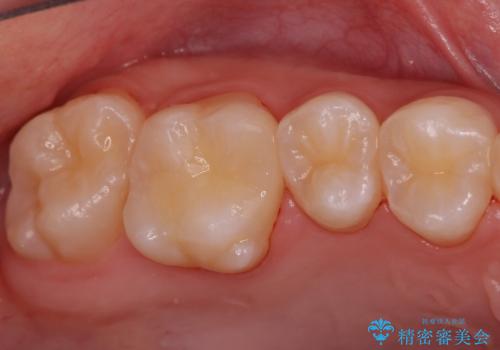

歯と歯の間の虫歯 セラミックインレーでの治療

- 検査の結果、レントゲン画像上で虫歯が確認されたため治療をしていくこととなりました。

白くて精度の高いものをご希望されたためセラミックインレーでの治療を行いました。

- 右上6 セラミックインレー 77,000円費用は治療当時の料金となります

小さな段差もないような適合の良い修復物は他の修復物に比べて今後の虫歯リスクを抑えることができます。